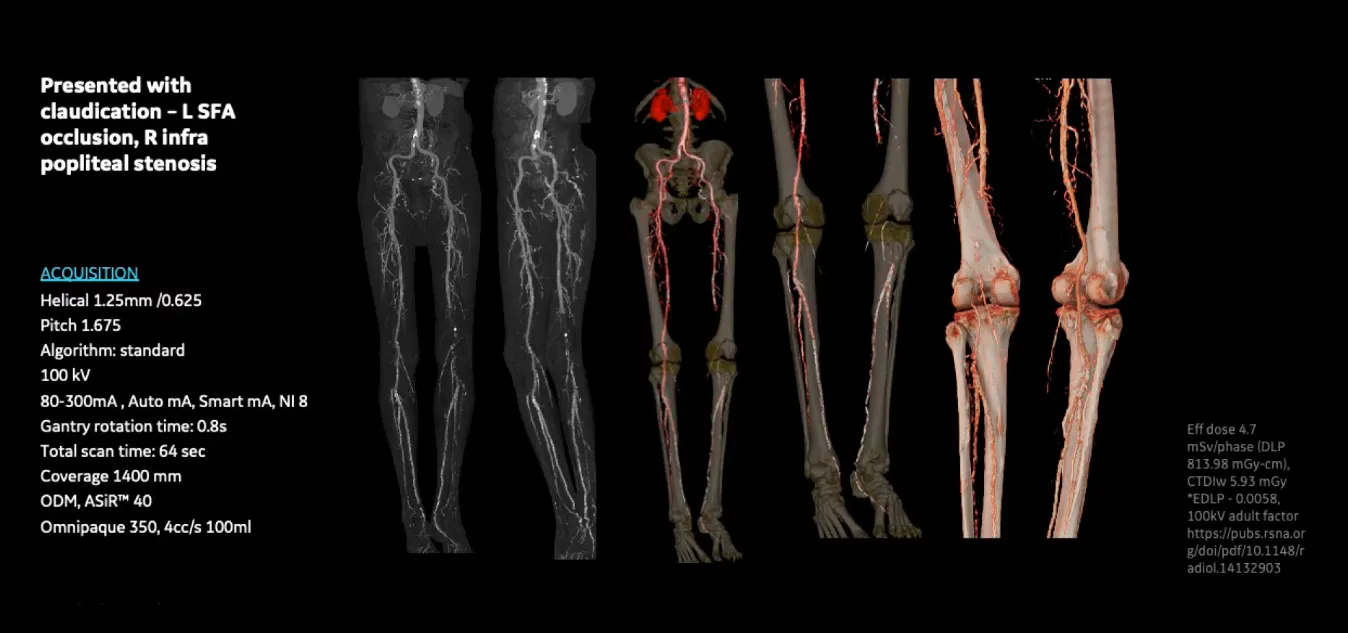

Клинические изображения

• Clarity Imaging Chain — комплексная цепочка визуализации для чётких и чистых изображений.

• IQE (Image Quality Enhancement) — улучшение качества изображения и снижение спиральных артефактов при тонких срезах.